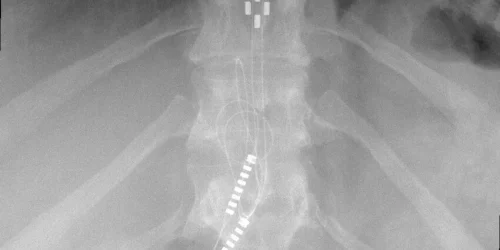

The doctor is then likely to call for an imaging test to assess the existing condition of the bone structure in the affected region. Soft tissues such as discs, nerve roots, ligaments, muscles, tendons, and cartilage are best examined with an MRI scan.

Doctors can also use x-rays to see whether there are any bone spurs or evidence of spinal degeneration. X-rays assist doctors in determining whether more medical imaging, such as a CT or MRI scan, is required. A CT scan is a type of x-ray that produces several cross-sectional images of the body. CT scans can better show nerves, bone, and soft tissue when contrast is injected into the cerebrospinal fluid placed in the intrathecal space.